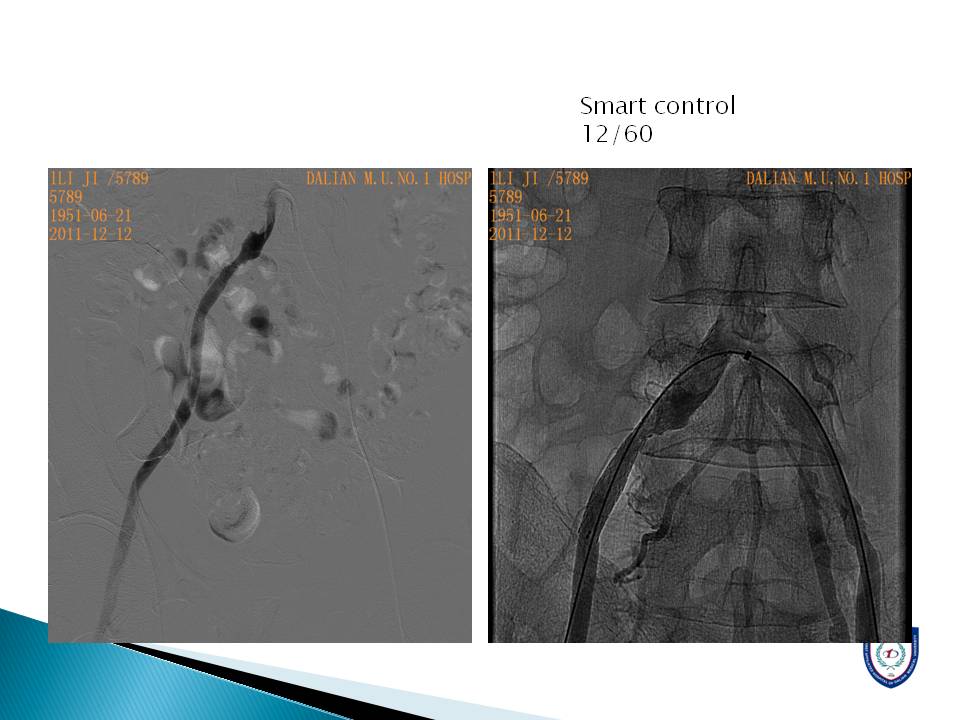

心房颤动导致的脑卒中和外周动脉栓塞的介入治疗